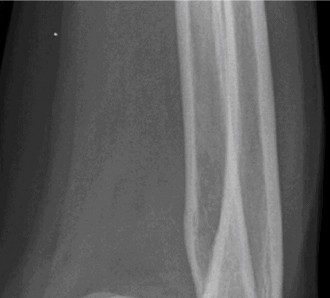

A 60-year-old female with a history of breast cancer treated 5 years ago with mastectomy, chemotherapy, and r…